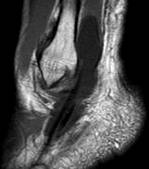

|

| РИС 1. Саггитальная плоскость сканирования. Т1 и Т2 ВИ. Стрелками указаны повышенное скопление жидкости в переднем и заднем заворотах, в полости суставов – большеберцово-таранном и таранно-пяточном. |